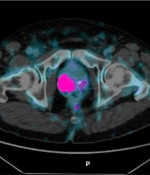

Analytical performance validation of aPROMISE platform for prostate tumor burden

García Vicente, A.M., Lucas Lucas, C., Pérez-Beteta, J. et al.

Scientific Reports 14, 3001 (2024)

Clinicopathologic and metabolic variables from 18F-FDG PET/CT in the prediction of recurrence pattern in stage I-III non-small-cell lung cancer after curative surgery.

G. Jiménez-Londoño, J. Pérez-Beteta, M. Amo-Salas, A. Honguero, V M. Pérez-García, C. Lucas, A. M. Soriano, A. M. García-Vicente

Annals of Nuclear Medicine 9 (2025)